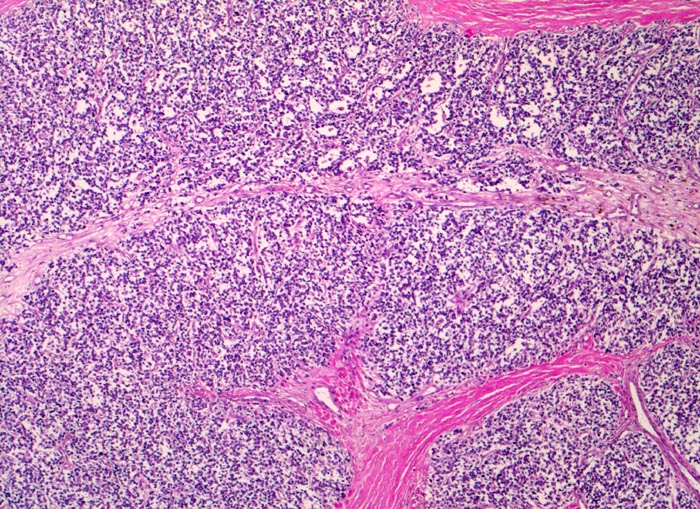

Morphologische Merkmale:

• Durch Bindegewebssepten abgegrenzte Knoten (lobuläre Architektur).

• Blauer, klein- und rundzelliger Tumor.

• Uniforme Zellen mit schmalem, kaum abgrenzbarem Zytoplasmasaum und unscharfen Zellgrenzen. Rundliche oder ovale Zellkerne mit leicht vergröbertem Chromatin und punktförmigen kleinen Nukleolen.

• Quetschartefakte (gequetschte Zellen sind dunkler und haben verkleinerte abgeflachte Zellkerne).